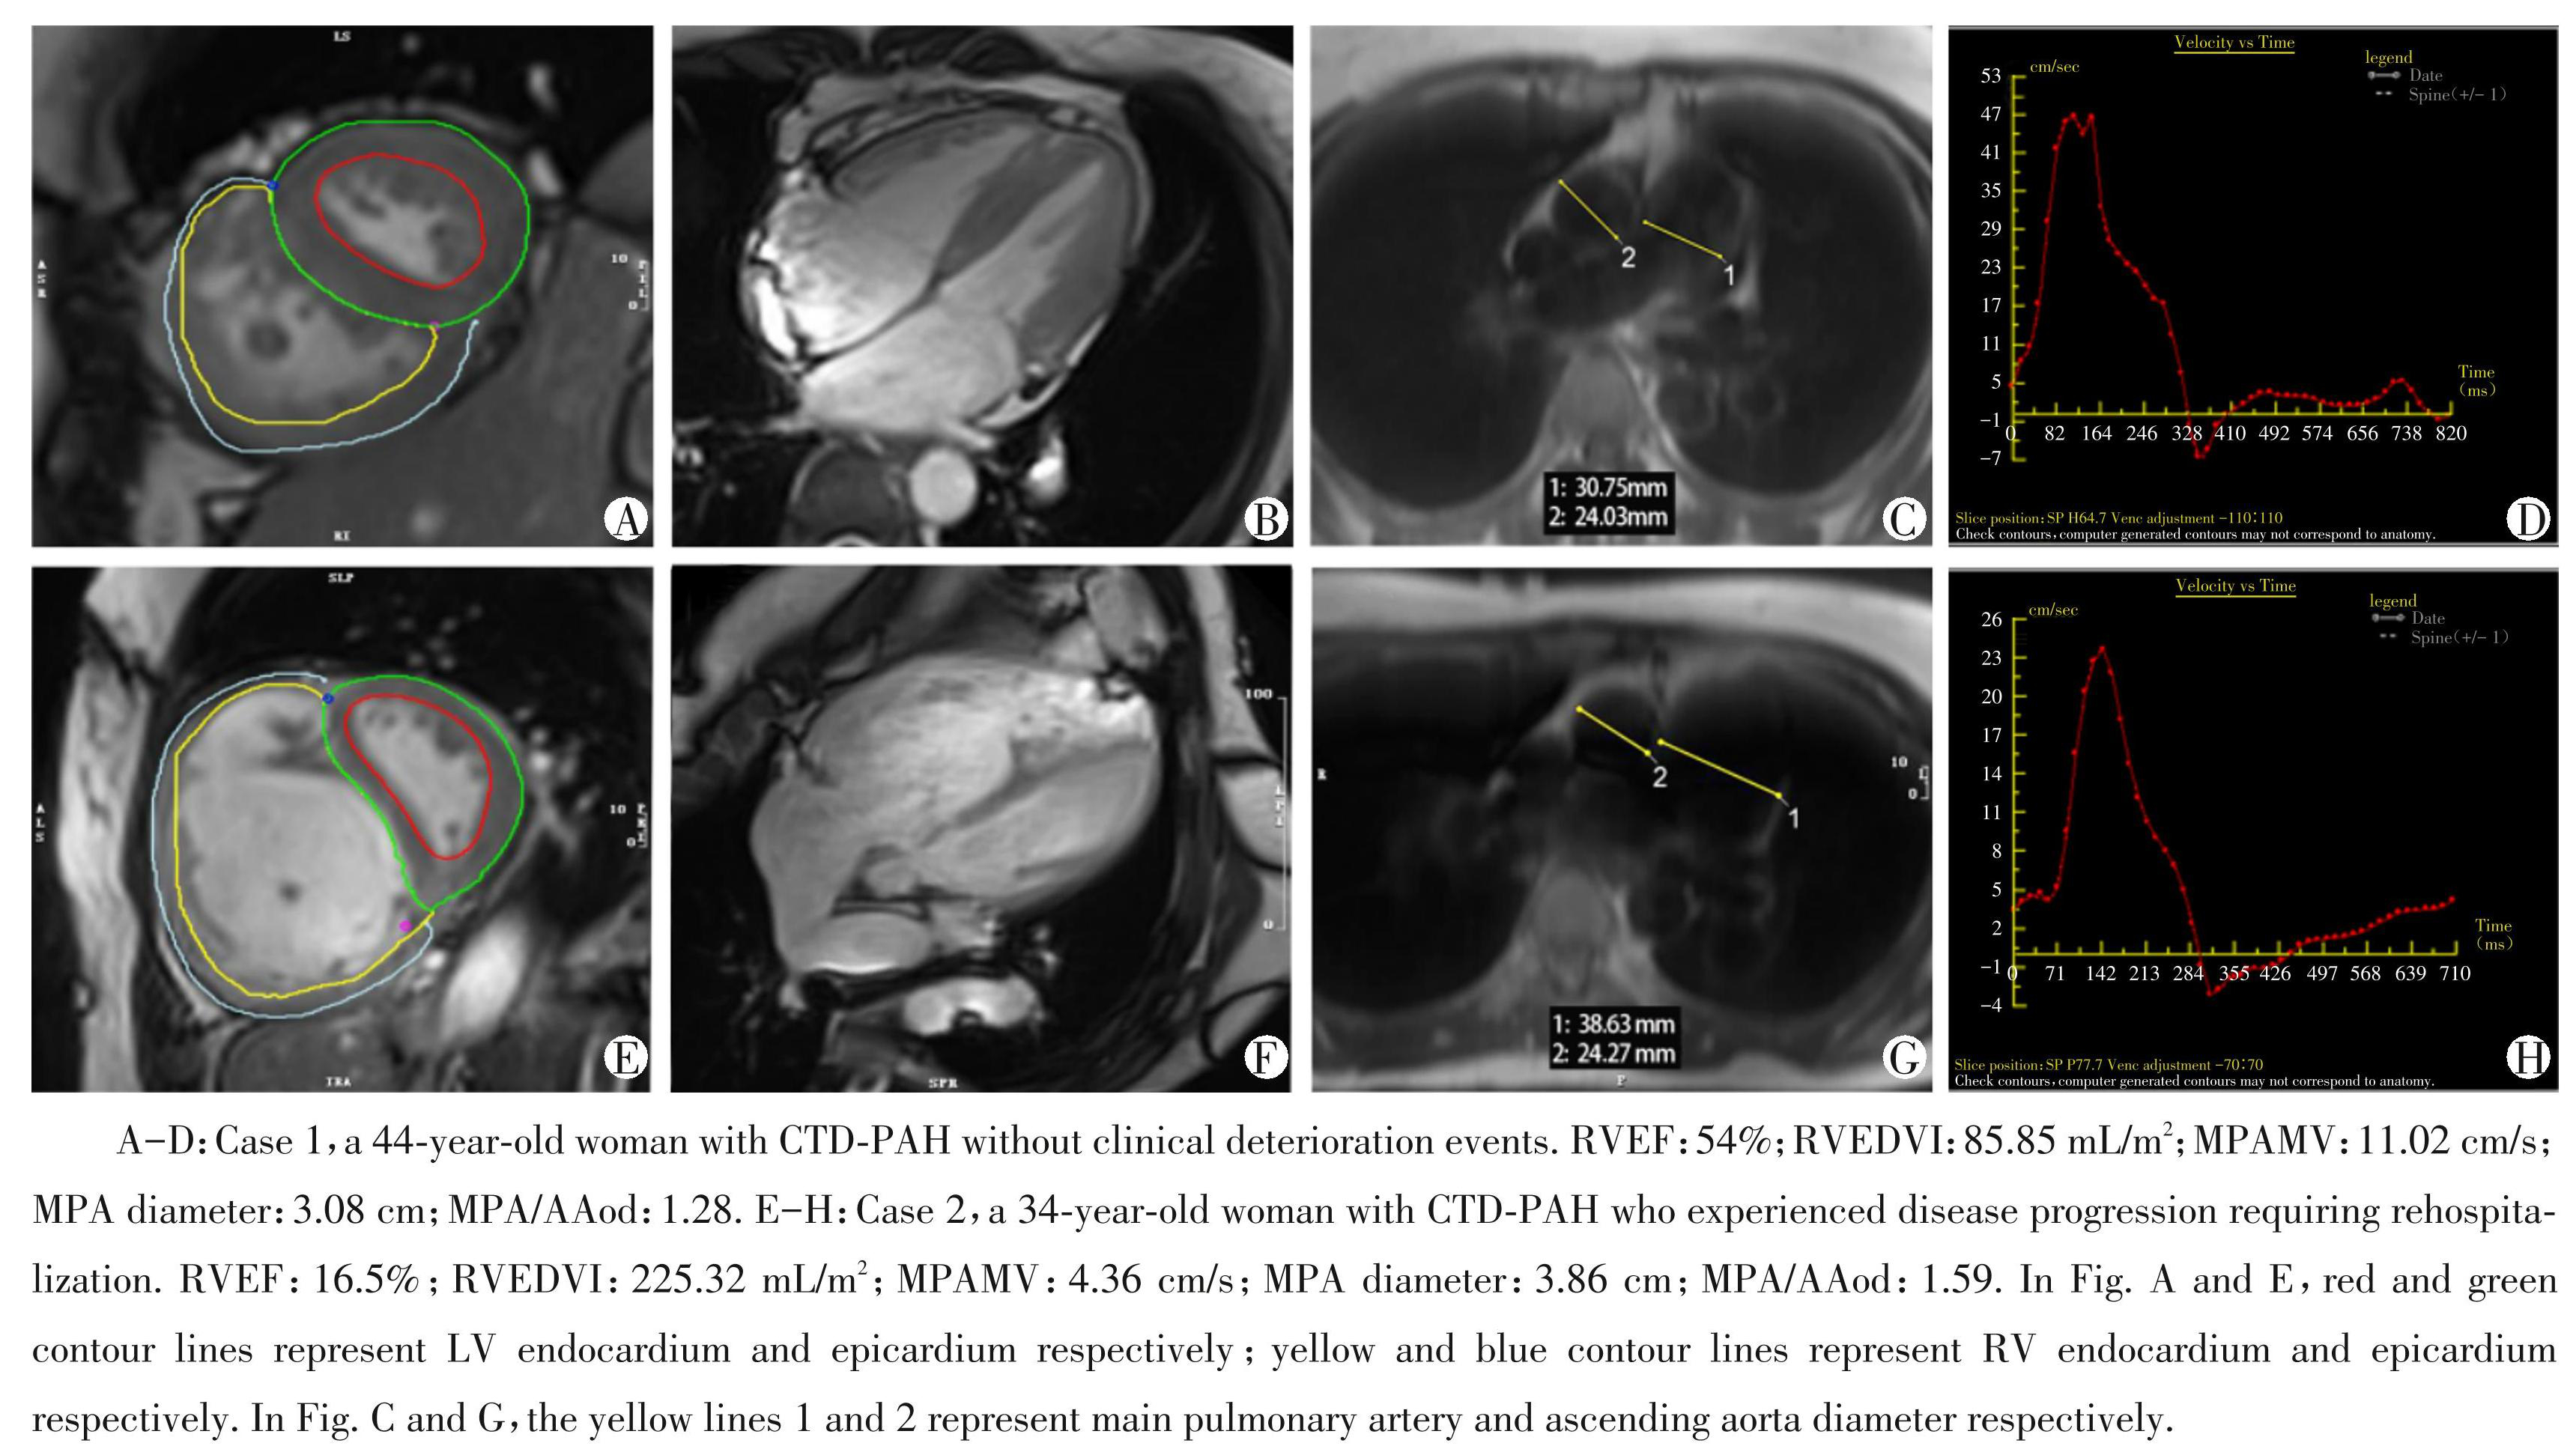

与未发生临床恶化事件组相比,发生临床恶化事件组CTD⁃PAH 患者的心功能参数LVEF、RVEF、 LVSVI、LVCI 均减低,RVEDVI、RVESVI、RVMMI 和 VMI 均升高。肺动脉血流参数 MPAPV、MPAMV 均显著下降。其余参数在两组间差异无统计学意义 (P >0.05,表1)。典型病例见图2。

图2未发生与发生临床恶化事件组CTD⁃PAH患者的典型病例图

Figure2Typical case charts of CTD⁃PAH patients in the groups without and with clinical deterioration events